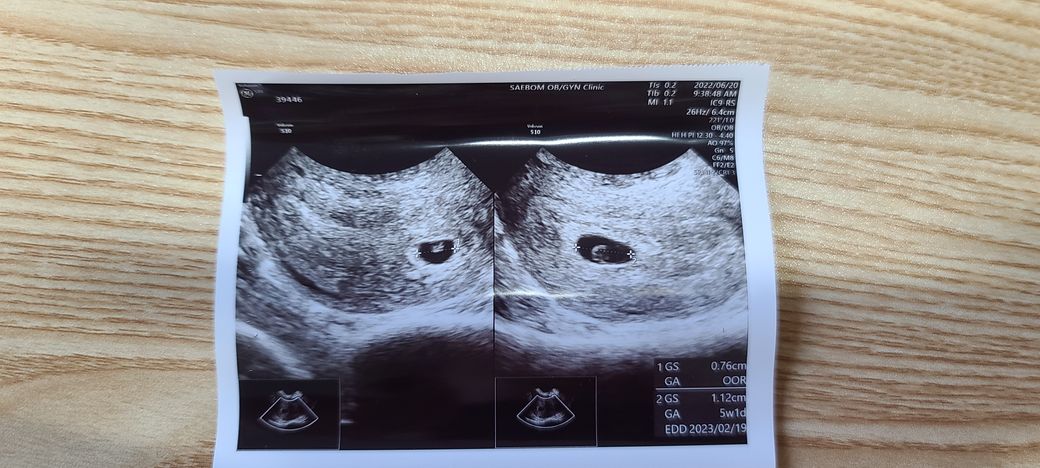

시험관으로 임신확인했고. 시술날로 계산하면 6주1일이에요.

지난 토요일 난임병원에서 초음파로 큰 아기집에만 난황이 있고 하루 느린상태라고 들었어요,

작은 아기집은 난황이 안보이고 더 많이 느리다고요.

진료보고 약간의 출혈이 있기도 하고 받은 초음파사진에 난황이 보이지 않아서,월요일 동네산부인과에 다녀왔는데, 초음파상으로는 5주1일밖에 안된다고..예후가 안좋을 수도 있다고 하네요ㅠㅠ

다른분들 난황은 다이아몬드 반지모양이던데, 저는 동그란 공 처럼 생기기도 했고요

제 초음파 상의 난황도 정상적인건가요??